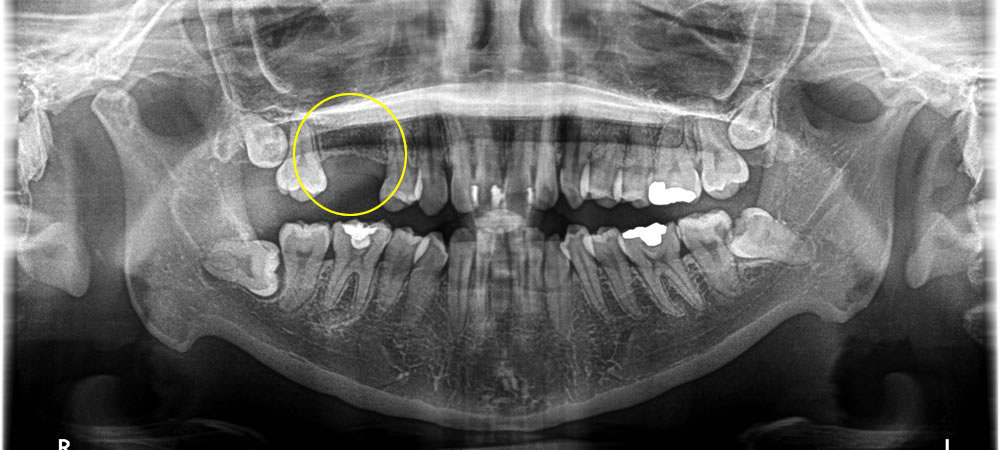

歯根破折した歯を抜歯してインプラントで治療した症例

年齢

40代

性別

女性